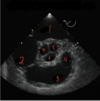

How well did you know this?

1

Not at all